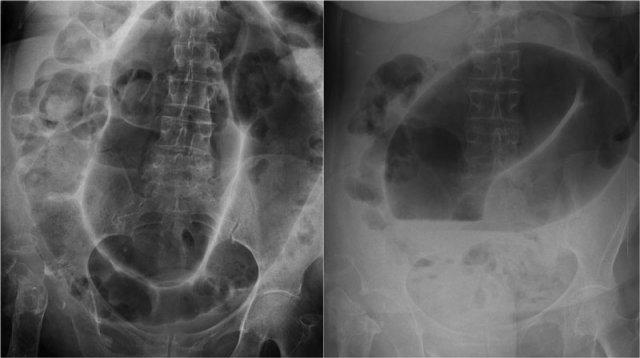

Bên trái là hình ảnh X-quang bụng thẳng của một nam bệnh nhân 57 tuổi với tiền sử đau bụng và chướng bụng tăng dần trong hai ngày.

Hãy quan sát hình ảnh trước rồi tiếp tục.

Ngoài hình ảnh giãn ruột lan tỏa, dấu hiệu chính trên phim này là một cấu trúc chứa khí lớn ở vùng chậu.

Chẩn đoán quan trọng cần nghĩ đến là xoắn đại tràng, và nhiều người sẽ chẩn đoán đây là xoắn đại tràng sigma do vị trí nằm ở vùng chậu.

Tuy nhiên, đây thực chất là xoắn manh tràng như sẽ được giải thích bên dưới.

Xoắn Manh Tràng

Xoắn ruột luôn lan rộng ra xa khỏi vị trí xoắn.

Do đó, xoắn đại tràng sigma chỉ có thể di chuyển lên trên và thường đi về phía góc phần tư trên bên phải.

Ngược lại, xoắn manh tràng có thể di chuyển đến hầu hết mọi vị trí và thậm chí có thể nằm ở vùng chậu (hình minh họa).

Bên trái là hình ảnh điển hình của xoắn manh tràng.

Chúng ta có thể thấy vùng chuyển tiếp hình mỏ chim nằm ở góc phần tư dưới bên phải, cho thấy đây là xoắn manh tràng.

Manh tràng giãn nằm ở góc phần tư trên bên trái.

Cũng lưu ý đại tràng xuống xẹp nằm phía sau manh tràng giãn (mũi tên cong).

Các hình X-quang cho thấy hình ảnh điển hình của xoắn manh tràng.

Lưu ý rằng quai ruột giãn hướng về phía vùng xoắn, đây là vị trí mà manh tràng thường nằm.